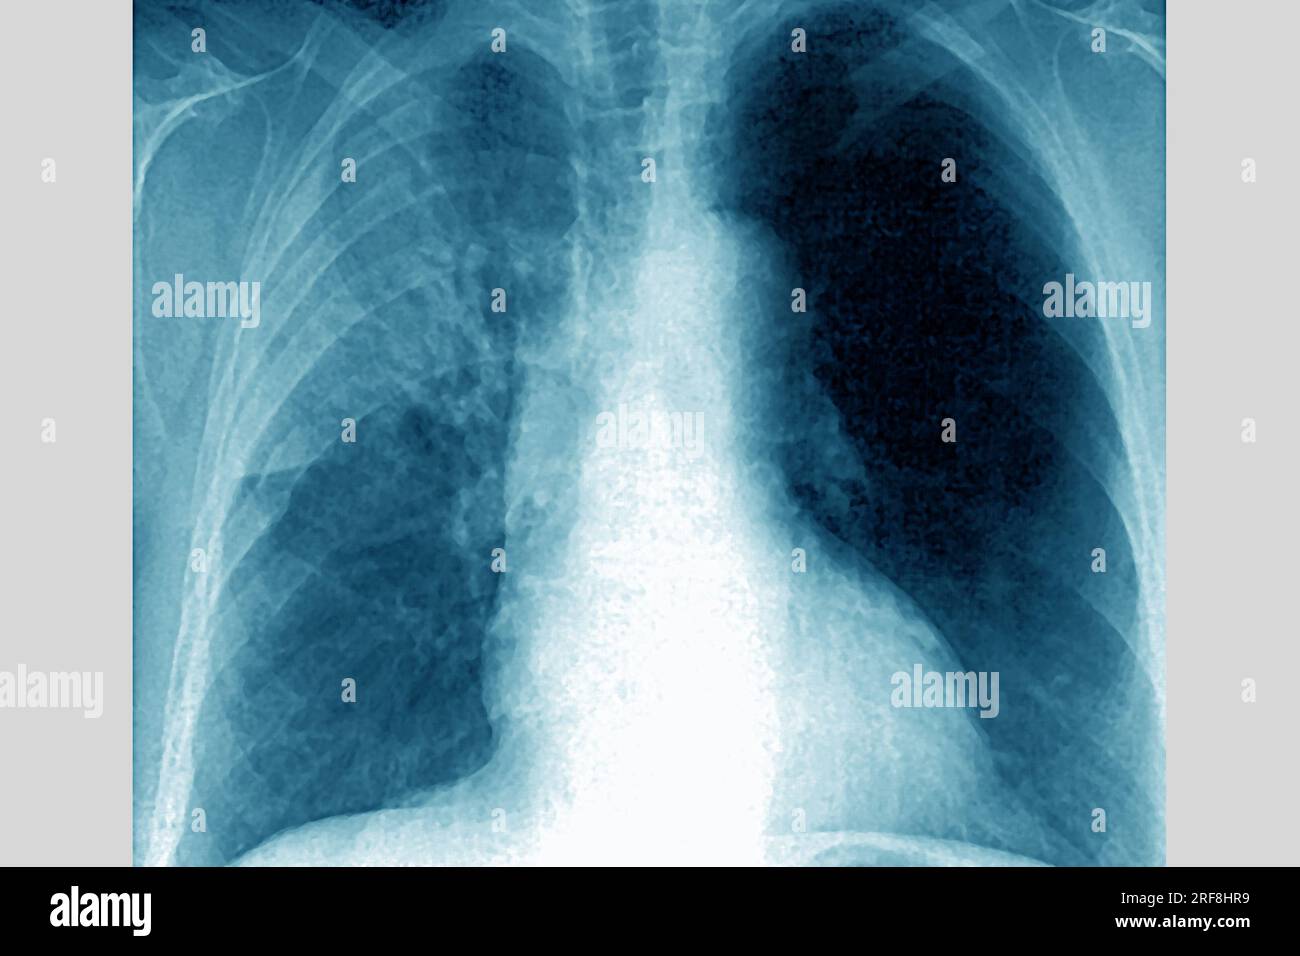

RM2RF8HR9–Pneumonie du poumon droit (infection respiratoire aiguë) révélée par une radiographie thoracique frontale.